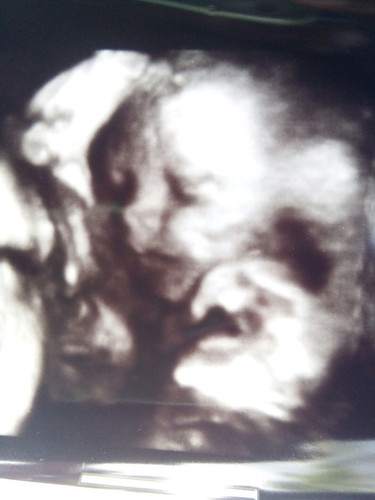

ชัดจังเลยค่ะ กี่มิติคะอันนี้

กำหนดคลอด 30ธันวา ค่ะ